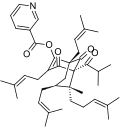

- Natural and semi-synthetic analogues of Hyperforin

-

-

Aristoforin

Aristoforin -

Hyperforin trimethoxybenzoate

Hyperforin trimethoxybenzoate -

Tetrahydrohyperforin

Tetrahydrohyperforin -

Hyperforin nicotinate

Hyperforin nicotinate